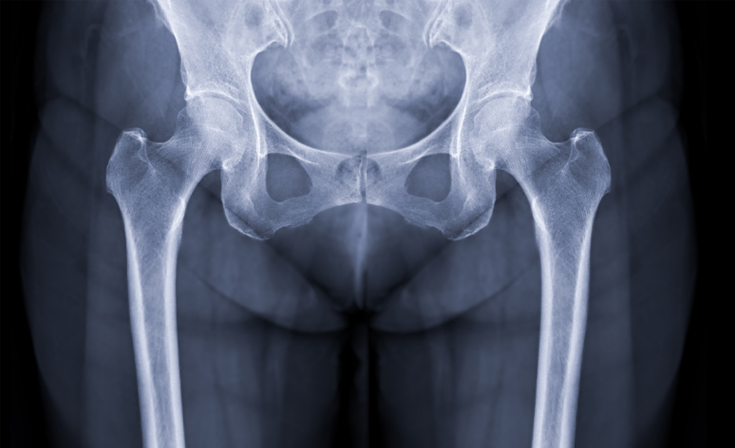

Hip

The hip joint is a ball-and-socket joint that connects the thigh bone (femur) to the pelvis, allowing for smooth and stable movement. While the hip is built for durability, injuries and degenerative conditions can significantly impact mobility and quality of life.

Common Hip Conditions & Injuries